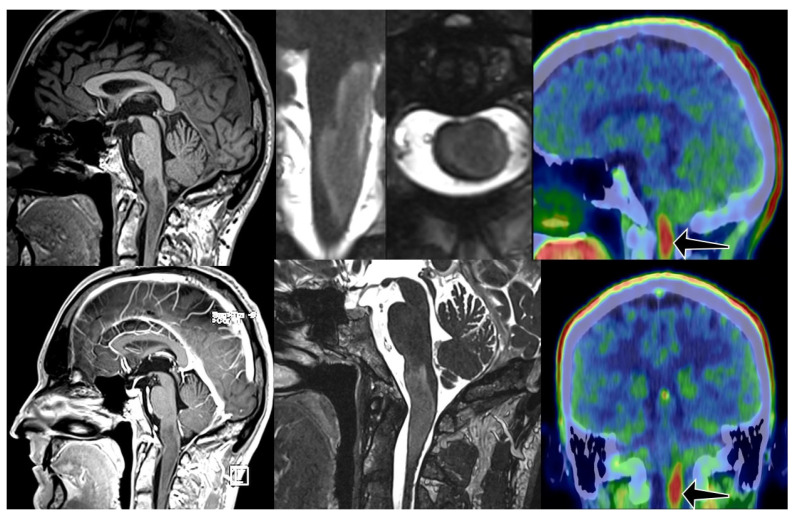

背景/目的:脑干胶质瘤的分类和分期有其自身的缺陷。手术活检仅在少数病例中可行。诊断主要依靠放射学特征。任何治疗都可能对生活质量产生重大影响;因此,正确和早期识别潜在的恶性病变是必不可少的,开始适当的治疗。氨基酸PET/CT与准确的代谢图谱可以帮助这一决策。方法:我们对2019年11月至2023年4月期间接受静态FET PET/CT检查的20例脑干病变不确定的患者进行了回顾性分析。我们使用多个肿瘤脑比(TBR)来评估显示长期和短期生存的患者亚组。结果:约登指数在TBR = 2.9时达到最大值。在此比率下,估计敏感性达到预期水平(91.7%),阳性和阴性预测值均处于良好的性能范围(68.8和75.0%),而特异性低于预期(37.5%)。结论:脑干胶质瘤的预后仍然具有挑战性。使用静态FET PET/CT可以更准确地检测高级别病变。在我们的分析中,我们发现TBR值为2.9最适合用于识别预后不良的患者。

Background/objectives: The classification and staging of brainstem glioma have its own pitfalls. Surgical biopsy is only possible in a small number of cases. Diagnosis relies mainly on radiological features. Any treatment may have a significant impact on quality of life; therefore, the correct and early identification of potentially malignant lesions is essential to initiate proper therapy. Amino acid PET/CT with accurate metabolic mapping can help in this decision-making.

Methods: We performed a retrospective analysis of 20 patients who underwent static FET PET/CT with uncertain brainstem lesions between November 2019 and April 2023. We used multiple tumor-to-brain ratios (TBR) to assess patient subgroups showing long-term and short-term survival.

Results: The maximum Youden index was reached at TBR = 2.9. With this ratio, the estimated sensitivity was at the desired level (91.7%), both positive and negative predictive values are in the good performance range (68.8 and 75.0%), while specificity was lower than expected (37.5%).

Conclusions: The prognosis of brainstem glioma remains challenging. The use of static FET PET/CT results in more accurate detection of high-grade lesions. In our analysis, we found a TBR value of 2.9 to be the most appropriate for identifying patients with a poor prognosis.